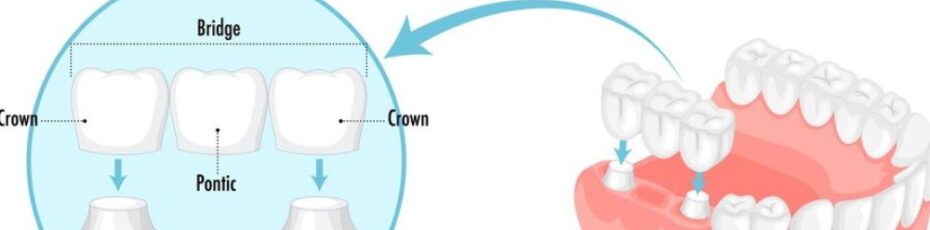

Dealing with a sharp, throbbing ache in your mouth can make it very hard to focus or sleep. When you visit a dentist near you to find a fix, the main goal is to stop the hurting and keep you healthy. While keeping your real teeth is always the first plan, sometimes a tooth is…